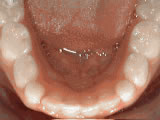

Non-braces treatment

Sometimes braces are not needed to get noticeable improvements in tooth alignment. This patient was first seen at age seven for crowding of the lower permanent teeth. A procedure was performed to reduce the width of the adjacent baby teeth and the permanent incisors aligned on their own in nine months.